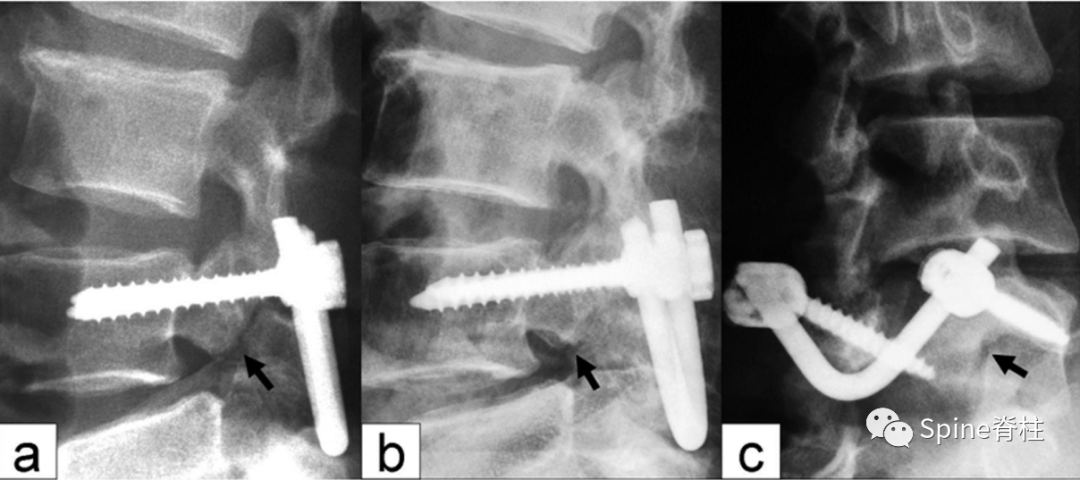

随着内固定的发展,既往峡部单纯修复植骨因融合率低、卧床时间长,现已很少应用。而植骨修复并节段固定有多种方法,包括Scott接线法、Buck螺钉法、Louis的蝶形板、钉钩技术(椎弓根螺钉和钩-棒系统)、U形棒等。从临床角度看,钉钩技术可以用刚性植入物固定断裂的峡部,并沿椎板方向施加作用力,有效稳定峡部,这对于达到更好的骨性愈合是至关重要的。理论上,此种方法更符合生物力学,对邻近节段影响小,但应把握好适应症,建议单纯腰椎峡部裂伴或不伴轻度滑脱患者可行植骨修复并节段固定。

1. 椎弓根螺钉-钉钩系统

PMID: 9199377

PMID: 15699811

PMID: 17520298